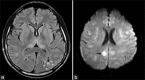

Butane is a commonly misused volatile agent, and a cause of intoxication. We present a case, who had a syncope and persistent ventricular fibrillation during the course of resuscitation. We discussed the management of this case in the intensive care unit and the accompanying difficulties in the light of the current literature.